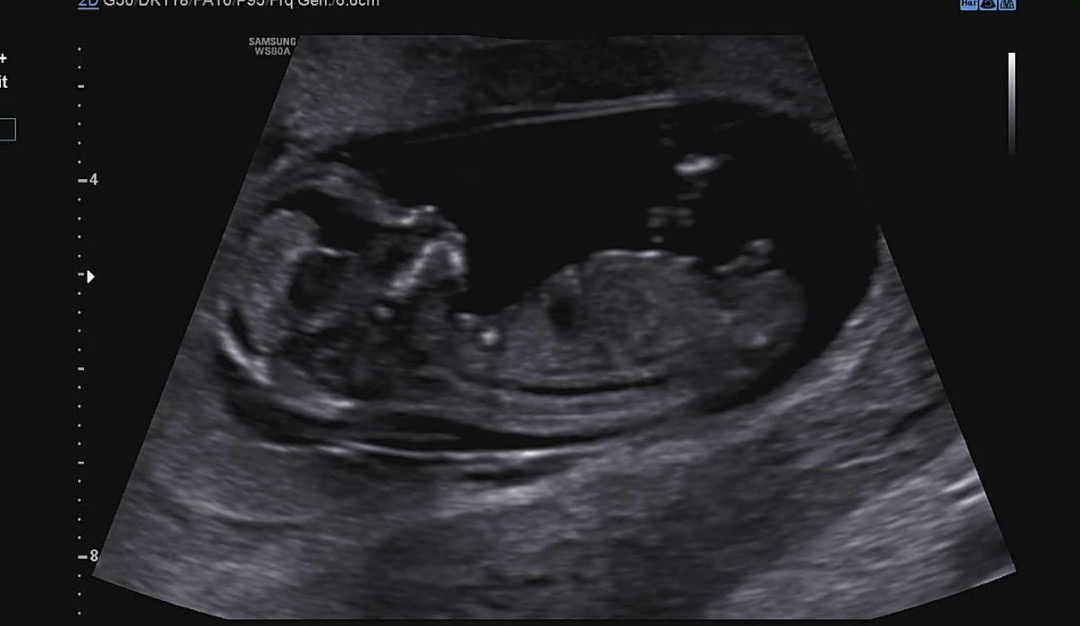

각도법 좀 봐주실 수 있을까요?

12주이고 딸인지 아들인지 궁금하네요

생식기가 굵은거 보니 아들이요

아들에한표요

아들 같아용